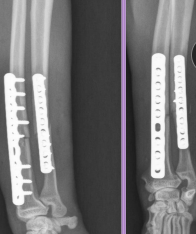

Radius & Ulna Fractures

Considerations: No soft tissue envelope, weight-bearing, blood supply poor in small breeds, poor healing, Robert/modified jones bandage

Tx: rigid fixation, often only radius tx

Bone plate & screws (#1)

IM pins contraindicated for radius

IM pins NOT in radius (cats need both)

JUST the radius in fixed(dogs)

External skeletal fixation→ open fractures, 1A ESF